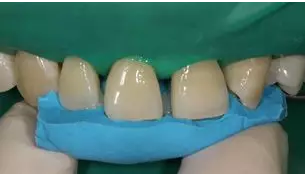

病例分享|復合樹脂微創(chuàng)美學修復關閉上前牙間隙

E2樹脂堆塑腭側釉質壁

移除硅橡膠導板后

D1 色,E2色分層堆塑完成